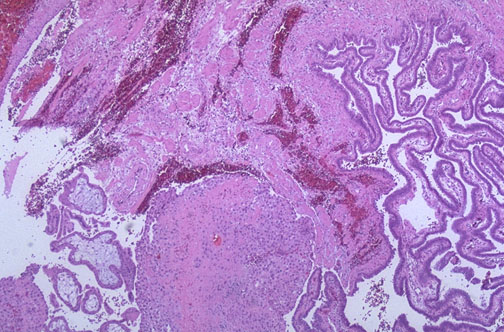

| A positive pregnancy test from the presence of human chorionic gonadotropin (HCG), ultrasound examination, and culdocentesis with presence of blood are helpful in making the diagnosis of ectopic pregnancy. Seen here is tubal epithelium at the right, with rupture site and chorionic villi at the lower left. |